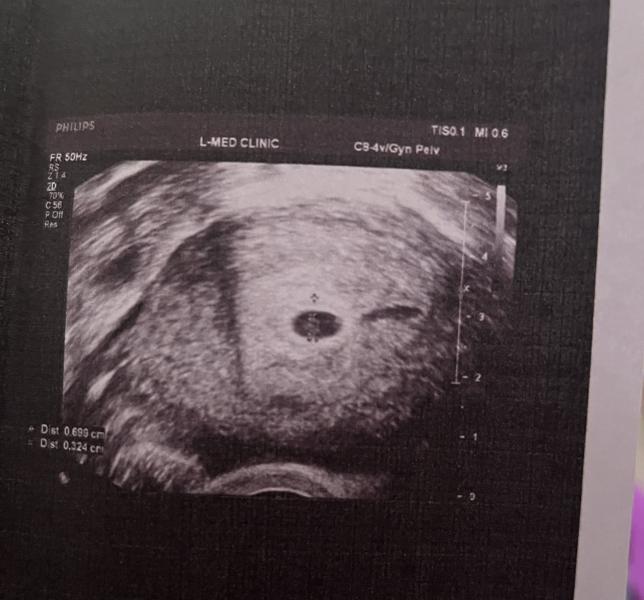

Беременность 5 недель

Нам 5 недель 🥰

Была поздняя овуляция

Сердцебиение пока не слышно, поеду на повтор УЗД через пару недель☺️❤️